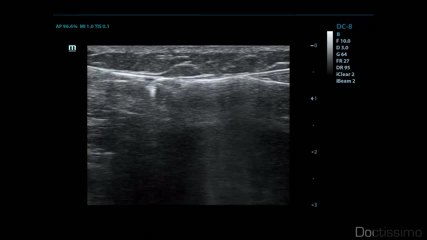

NuSkin - Traitement des varices et varicosités